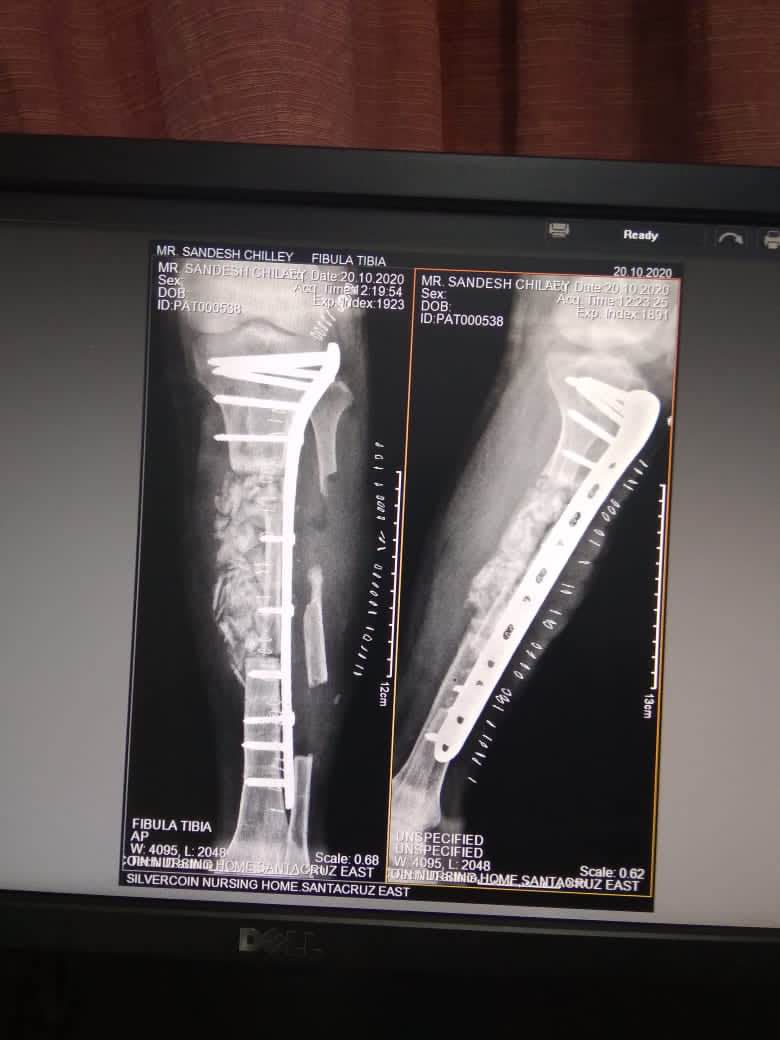

Best RECONSTRUCTION SURGEON IN Andheri and Santacruz